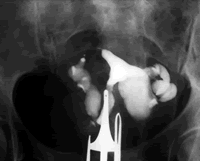

输卵管伞端成形术 当输卵管伞端被包裹时可导致远端输卵管的部分闭锁,这时需进行输卵管伞端成形术。手术包括分离输卵管伞端周围的盆腔粘连,游离出输卵管伞。对于严重的输卵管伞端包裹,一项跟踪随访2年的研究表明,腹腔镜治疗有51%的宫内妊娠率,31%的胎儿成活率,23%的宫外妊娠率。

输卵管积水的治疗 输卵管积水可造成远端输卵管的完全闭锁。重新修建输卵管结构的手术为输卵管造口术。造口术疗效依赖于输卵管破坏的程度。总的来说,疗效不甚理想。造口术后的平均妊娠率为30%,宫外妊娠率为5%。通常情况下,输卵管造口术只推荐用于远端输卵管损害很轻微的年轻患者。

在进行体外受精(IVF)之前也应对输卵管积水进行外科治疗,因为输卵管积水会减少IVF成功妊娠的机会。这可能是由于输卵管中的积液流进腹腔,危害胚胎所致。积液还有可能冲走宫腔内的胚胎,使其无法种植。一项荟萃分析表明,输卵管积水可使妊娠率降低50%,而输卵管造口术可显著提高妊娠率和胚胎成活率。